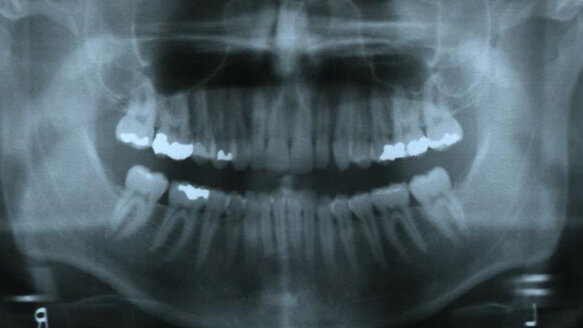

TMJs and facial musculature were asymptomatic. CR-CO slide was within normal limits. Periodontal examination showed no recession and adequate attached tissue, with a PSR score of 1 with slight bleeding on probing upper right. The patient had good oral hygiene. Third molars were absent, with moderate restorative history on teeth #2, 3, 4, 5, 13, 14, 15, 30 but no active caries. Areas of enamel hypoplasia and cervical decalcification were present.

The records taken included: photographs, a panoramic radiograph, centric occlusion bite registration and PVS impressions. The maxillary arch exhibited a mixture of crowding and spacing with a net of 0 mm arch length discrepancy. The mandibular arch exhibited 2.5 mm arch length discrepancy. The maxillary midline was right 1 mm and the mandibular midline left 1 mm. The patient had a Class I right, Class I left (1 mm discrepancy) molar relationship, with a Class I right, end-on Class II left canine relationship. Transverse maxillary/mandibular archforms were narrow. The patient had an overjet of 4 mm, and an overbite of 4 mm as well (see Figs. 4-9).